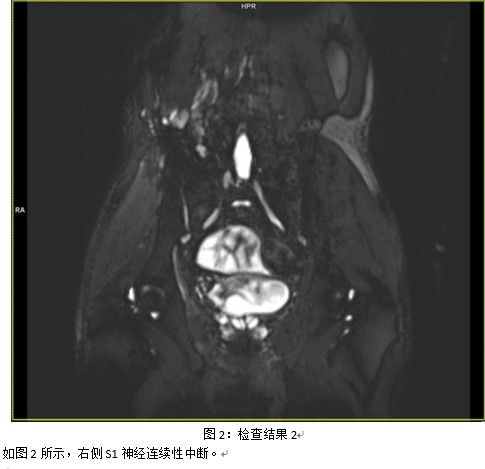

神经损伤的分级:评估及区分单纯神经牵拉损伤及神经相连的神经瘤及神经断裂。

实例说明